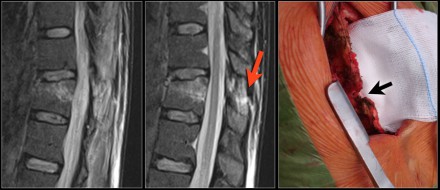

Here another distraction injury.

At surgery the rupture of the supraspinous ligament was confirmed (red and black arrows)